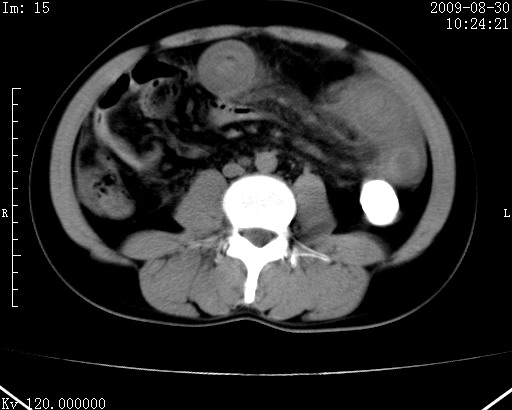

患者唐某,男31岁,已婚,本地务农。

自述入院前两天一次进食较多冷饮之后,出现阵发性上腹部疼痛,次日加剧伴恶心、呕吐,呕吐后症状稍减轻。食欲差。大便每天1-2次,量少,暗红色水样。小便赤。无畏寒、发热、咳嗽等呼吸道症状。无高血压及胃病史。

检查:体温、血压及脉搏正常.皮肤无黄染,浅表无淋巴结肿大。左腹肌紧张,左上腹有压痛,无反跳痛,可触及包块。

生化:钾、钠、氯、钙、ph正常,总胆红素和直接胆红素稍高,空腹血糖稍高。

尿淀粉酶:1256 u/l(正常60-401)。

血常规:wbc 22.4x109/l gr88% ly9.6%其余基本正常。

胃镜:急性胃炎。立位腹平片:未见异常。

下面是ct平扫,降结肠内是对比剂。

术前影像诊断:上段空肠急性缺血性坏死并腹水。建议手术治疗。

术中见上段空肠约70cm长范围坏死,从屈氏韧带远端约10cm处开始。坏死肠管肿胀变形变色,管壁明显环形增厚,部分聚成大肿块,无扭转和套叠。肠系膜上动脉分支内广泛泥沙状血栓。肠切除。

临床诊断:肠系膜上动脉梗塞并急性肠坏死。

开始时我们科也有人认为是套叠,最后统一意见,不考虑肠套。我们看到的“靶征”,“晕圈征”,“双圈征”实际上只是单根肠管的横断面。坏死肿胀后肠壁各层的密度不一样。

左侧腹小肠腔管壁明显增厚,部分内示靶征,走行异常,部分肠系膜绳样改变,肝包膜下及肠间较多液体密度,然梗阻近端肠腔积气不明显。

考虑;肠扭曲伴肠坏死。